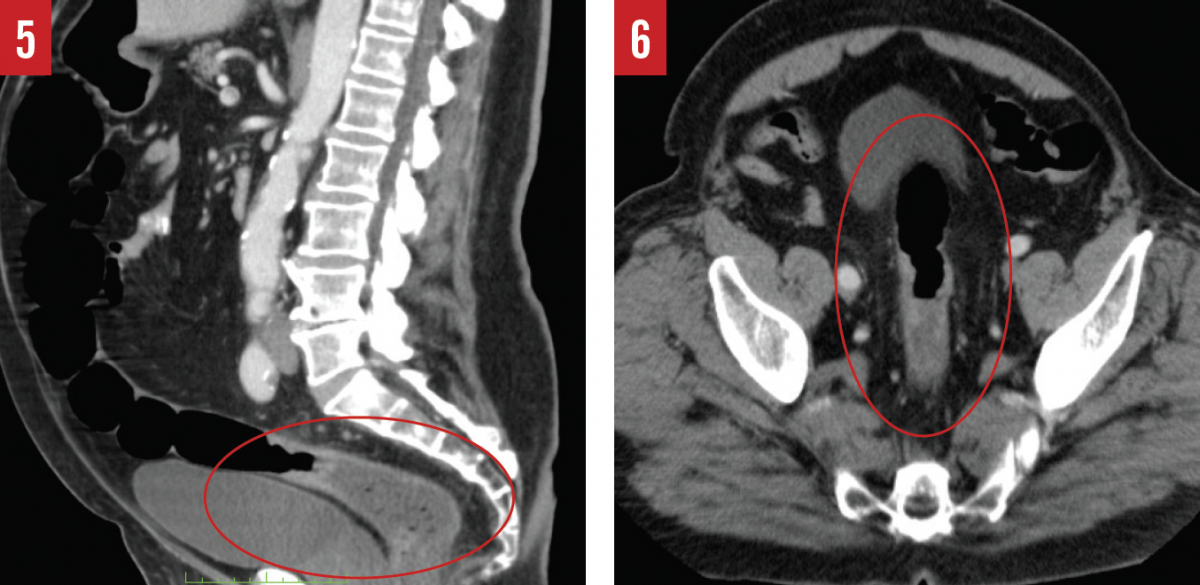

The scope was advanced to the anastomosis, and it was noted that no mass remained in the colon. Upon withdrawal of the colonoscope, however, a second mass measuring approximately 4.5 × 3.0 cm that had not originally been noticed on CT was discovered in the rectosigmoid junction (Figures 5 and 6). Biopsies were obtained and examined histologically, revealing that this mass was a stage IIIA low-grade adenocarcinoma with invasion into the muscularis propria and regional lymph nodes.

In the example case presented here, the surgeon visualized a mass in the hepatic flexure that he perceived to be in the cecum. The CT imaging and radiology report corroborated this finding, stating that there was a cecal mass but with no mention of a mass in the hepatic flexure or in the rectosigmoid junction. Nevertheless, on second look, the hepatic flexure mass was apparent on images in all 3 viewing planes, and the rectosigmoid junction showed wall thickening that should have been flagged as abnormal for further workup, as well.